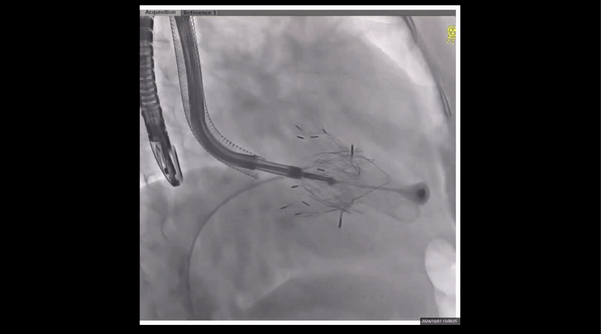

術前右室造影

夾持件位置確認

室間隔位置確認

術中經食道超聲輔助下可見LuX-Valve Plus夾持件抓捕瓣葉狀態良好,夾持件在位,室間隔錨定位置良好,假體瓣膜整體錨定狀態穩固。

瓣膜釋放